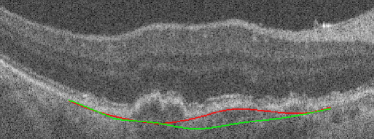

Bruch’s Membrane is an elastic smooth and thin structure, strategically located between the retina and the general circulation, having a crucial role in retinal function, aging and disease [14]. Automated segmentation of the BM is particularly important in the context of AMD as, unlike other common retinal diseases such as DR, RVO, or glaucoma, the BM is distinguishable from the outer RPE boundary. In specific, drusen in iAMD and PEDs in nAMD separate the RPE from BM, requiring the segmentation of the region in-between them. In addition, in case of GA, the RPE is completely lost in some locations, exposing only the BM, thus imposing additional difficulties for algorithms and calculations that depend on the RPE position. Achieving correct automated identification of the BM is challenging in many cases, mainly due to the small thickness of this layer, the high reflectivity of the RPE that shadows parts of the BM, and the noise being present in the scans, which is often indistinguishable from the content of drusen and PEDs (Fig. 4). Due to these difficulties, currently many automated solutions either do not provide a segmentation of the BM or its segmentation is often inaccurate in retinal OCT with AMD, leaving this clinically relevant segmentation task unaddressed or under-explored.

(c) GA

A representative example of the influence of the curvature term is shown in Fig. 17. The proposed method with the help of the curvature term correctly finds the BM as opposed to Proposed w/o w/o TPS. The associated uncertainty is also adequately higher, signaling the lower confidence of the BM position estimate in this region. In contrast, the absence of leads to a poor uncertainty estimation in some incorrect segmentation regions.

(a)

(b)